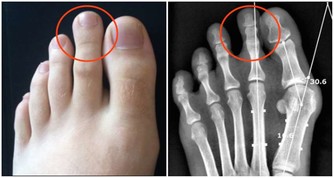

腳趾:兩腿伸直,低頭,身體向前彎,以兩手扳足趾關節各20—30次,能鍛鍊腳力,防止腿足軟弱無力。